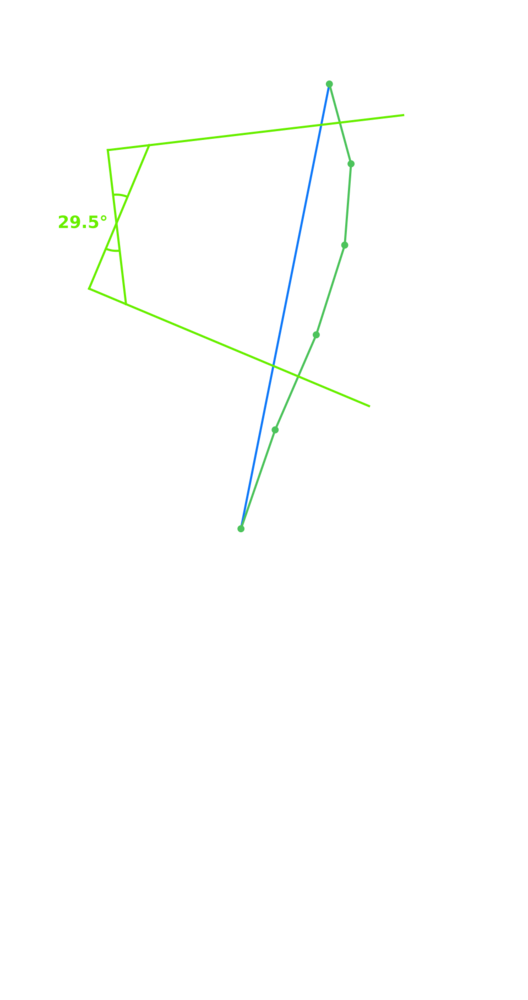

ИИ и алгоритмы интеллектуального анализа рентгеновских снимков позвоночника. Позволяет обнаружить математически обоснованные искривления позвоночника и костные аномалии менее чем за 30 секунд